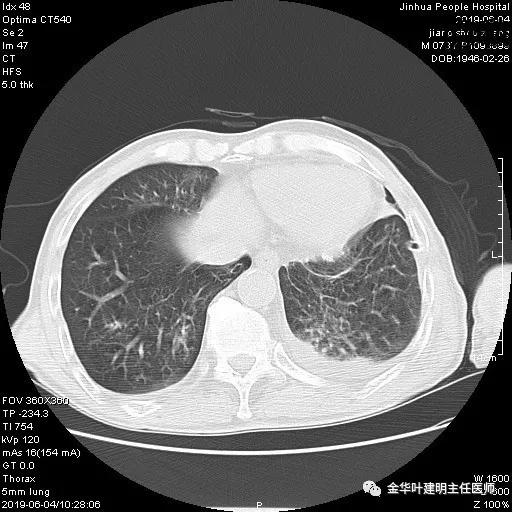

6.4上午:24小时引流出血性乳糜液1800毫升。是否再次手术进行右进胸胸导管结扎,抑或继续保守治疗非常纠结!压力非常大!!多方讨论会诊无法取得一致意见,但一般认为,引流量在1000毫升以上宜积极手术。情况与浙二医院范军强教授联系,请求指导,范教授认为左侧肺手术,损伤胸导管主干的机会较小,多数可保守治疗而愈。在他们的病例中,也有结扎胸导管后引流量仍无减少,效果并不能完全保证。建议可以考虑胸管夹管观察(因为淋巴管压力低,予以适当的压力,漏出量可能会明显减少),同时继续禁食,并静脉营养支持,引流管口可能会有渗液,注意更换敷料。与家属充分沟通后决定试夹管;这天血色素9.0 g/L;胸部CT复查示: